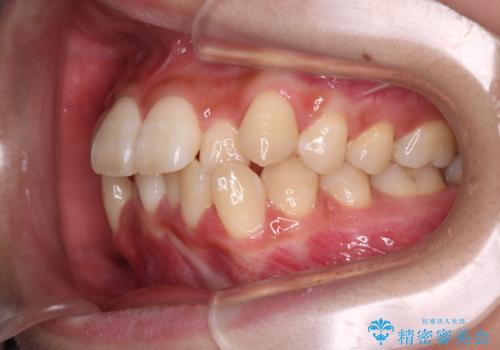

反対咬合を治したい。インビザライン

- 前歯の反対咬合を治したいことを主訴に来院されました。

インビザラインにて臼歯の遠心移動を行いながら、スペースを作り反対咬合を改善することができました。